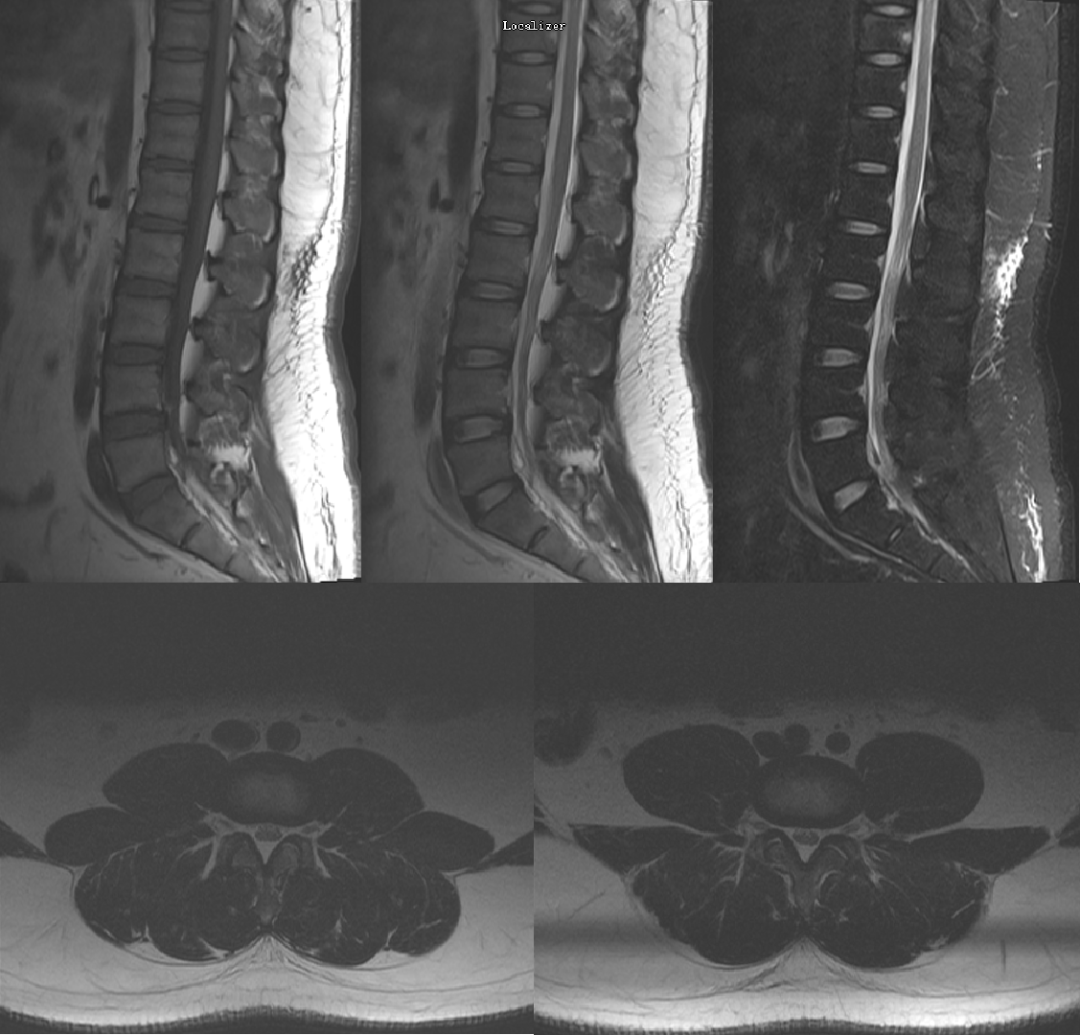

病例一

男,45 岁,1 年前出现慢性腰痛、双侧大腿麻木和无力感。临床查体无神经功能缺损。

本次腰椎 MR 检查:你发现了什么?

4.5 年前腰椎 MR 检查

4.5 年前和现在的腰椎 MR T2WI 轴位对比:L4-L5 水平,现在的 MR 发现马尾神经位置前移,更加聚拢;而 4.5 年前的 MR 发现马尾神经位置靠后,分散。

回过头再看第一个病例,发现椎管内硬膜外脂肪增多,向前推挤马尾神经,使其相对聚拢

回过头再看第二个病例,发现椎管内背侧硬膜外脂肪增多,超过椎板前缘,向前推挤马尾神经,使其明显聚拢

同样的,回头看第一个病例也会发现硬脊膜椎韧带,是由于硬膜外脂肪增多而把他显示出来